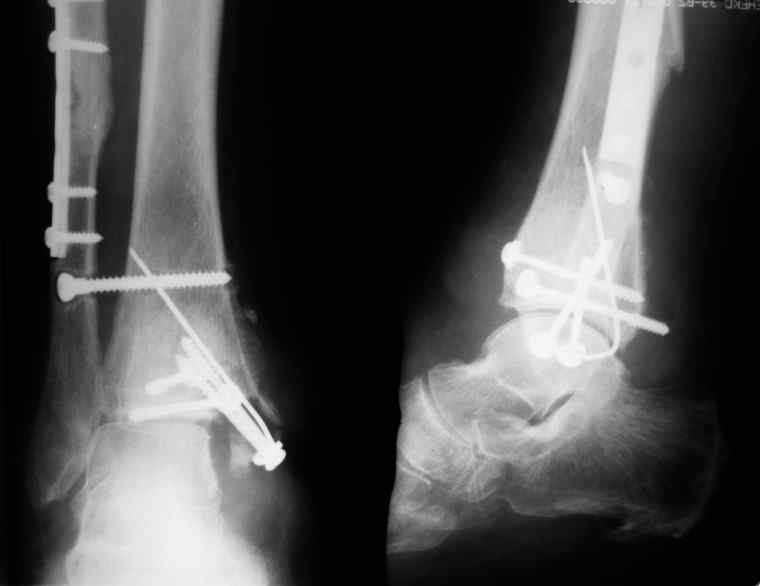

31 августа 2007 года была оперирована в другой области по поводу DS Закрытого двухлодыжечного перелома правой голени с подвывихом стопы кнаружи , кзади. Разрыв дистального межберцового синдесмоза. Перелом заднего края большеберцовой кости справа. Поступила в наше отделение со швами ,с некрозом медиальной поверхности правого голеностопного сустава. Проведено : снятие швов , антибиотики , некрэктомия с последующей кожной пластикой .Заживление 20 декабря 2007 года ,выписана из стационара . 3 марта 2008 года поступает с гиперемией , отек , флюктуацией. В настоящее время имеется рана по медиальной поверхности правой голени ,отеки и гиперемия сохраняется .Наша тактика:1) снятия воспалительного процесса, 2) удаление металлоконструкции, 3) выполнения артродеза правого голеностопного сустава.

Не очень удачный вариант остеосинтеза: сохранен подвывих стопы, синдесмоз не достаточно репонирован. Думаю, в данном случае у пациента д-з: остеоартрит правого голеностопного сустава, послеоперационный остеомиелит правой голени. Предлагаю тактику: одномоментно выполнить удаление металлоконструкции, хирургическую обработку очага остеомиелита, резекцию голеностопного сустава, артродез аппаратом. Другие методы лечения не привидут к купированию гнойного процесса. Так как полость сустава в настоящее время имеет вид пиогенной капсулы, в которой будет поддерживаться гнойный процесс даже после заживления свища, с последующим его открытием и опорожнением гноя.